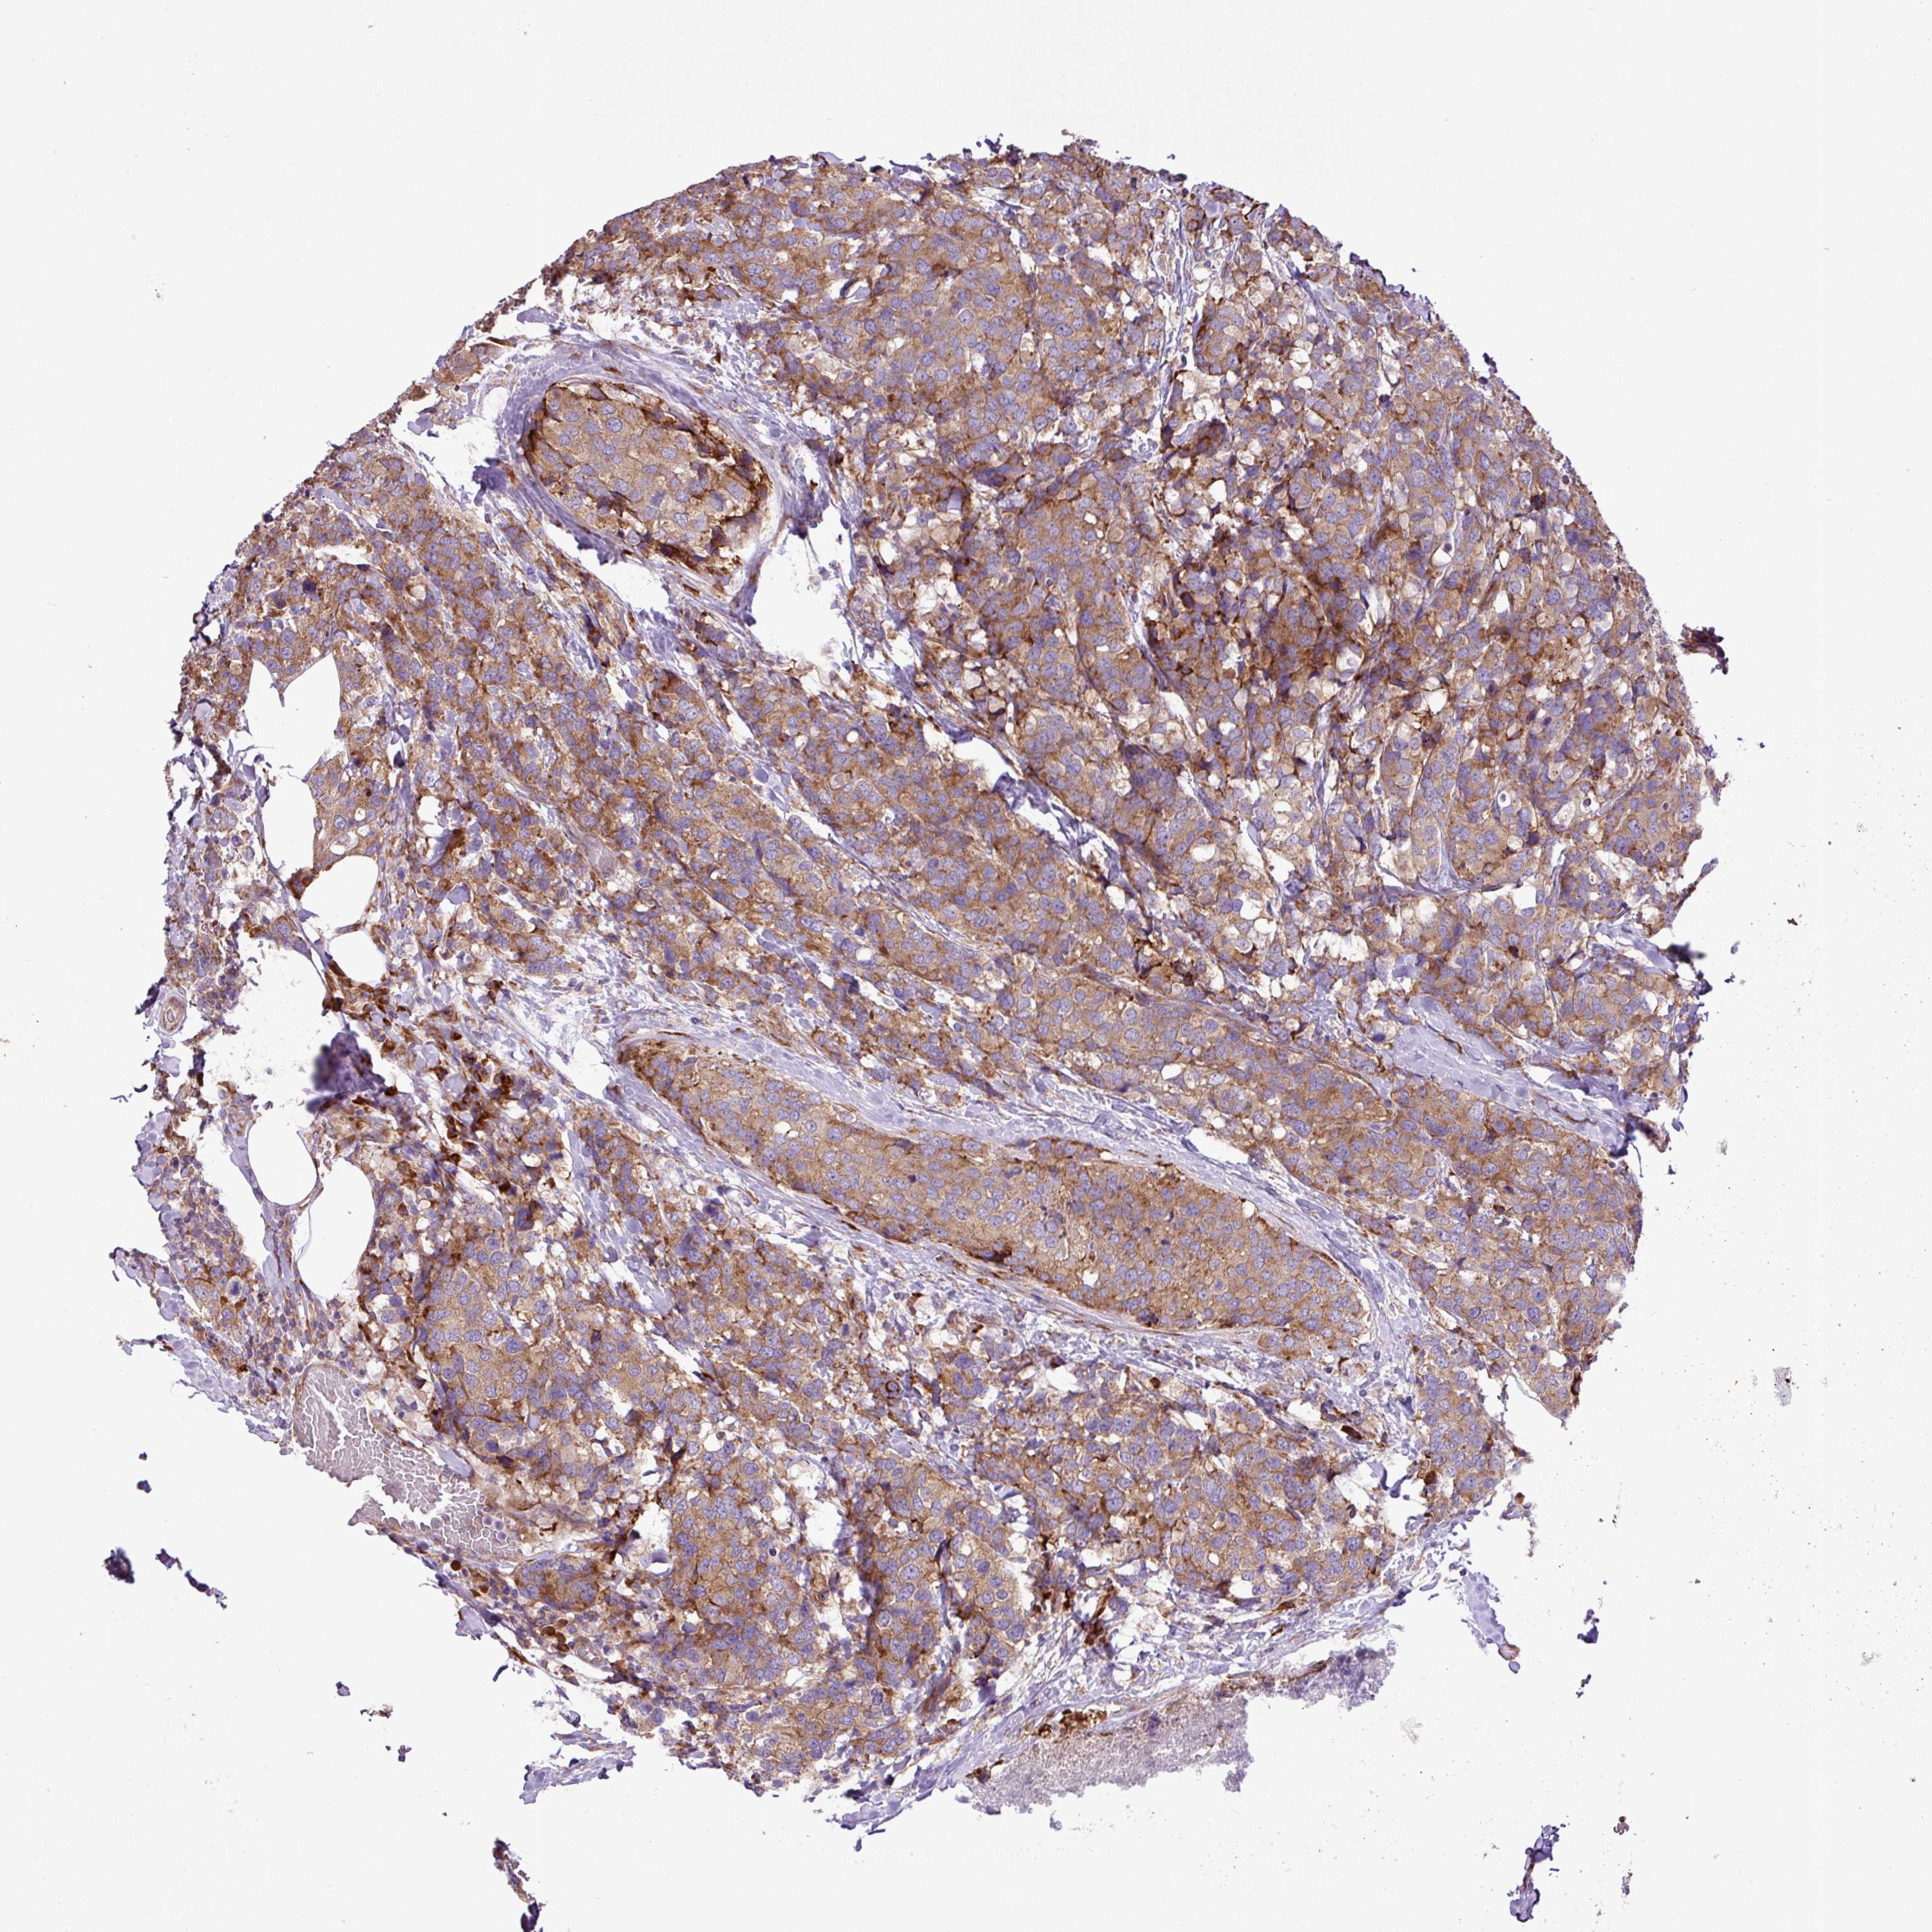

CANCER BREAST CANCER Show tissue menu

Breast cancer

Human cancer